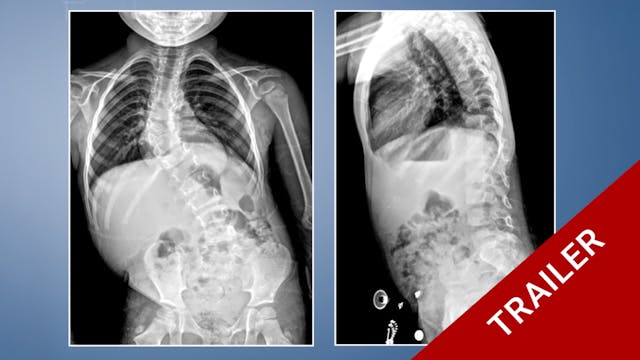

Project 14-015

This film demonstrates an anterior cervical approach, the surgical strategy in a case of multilevel cervical myelopathy and a cervical corpectomy strategy in a revision surgery